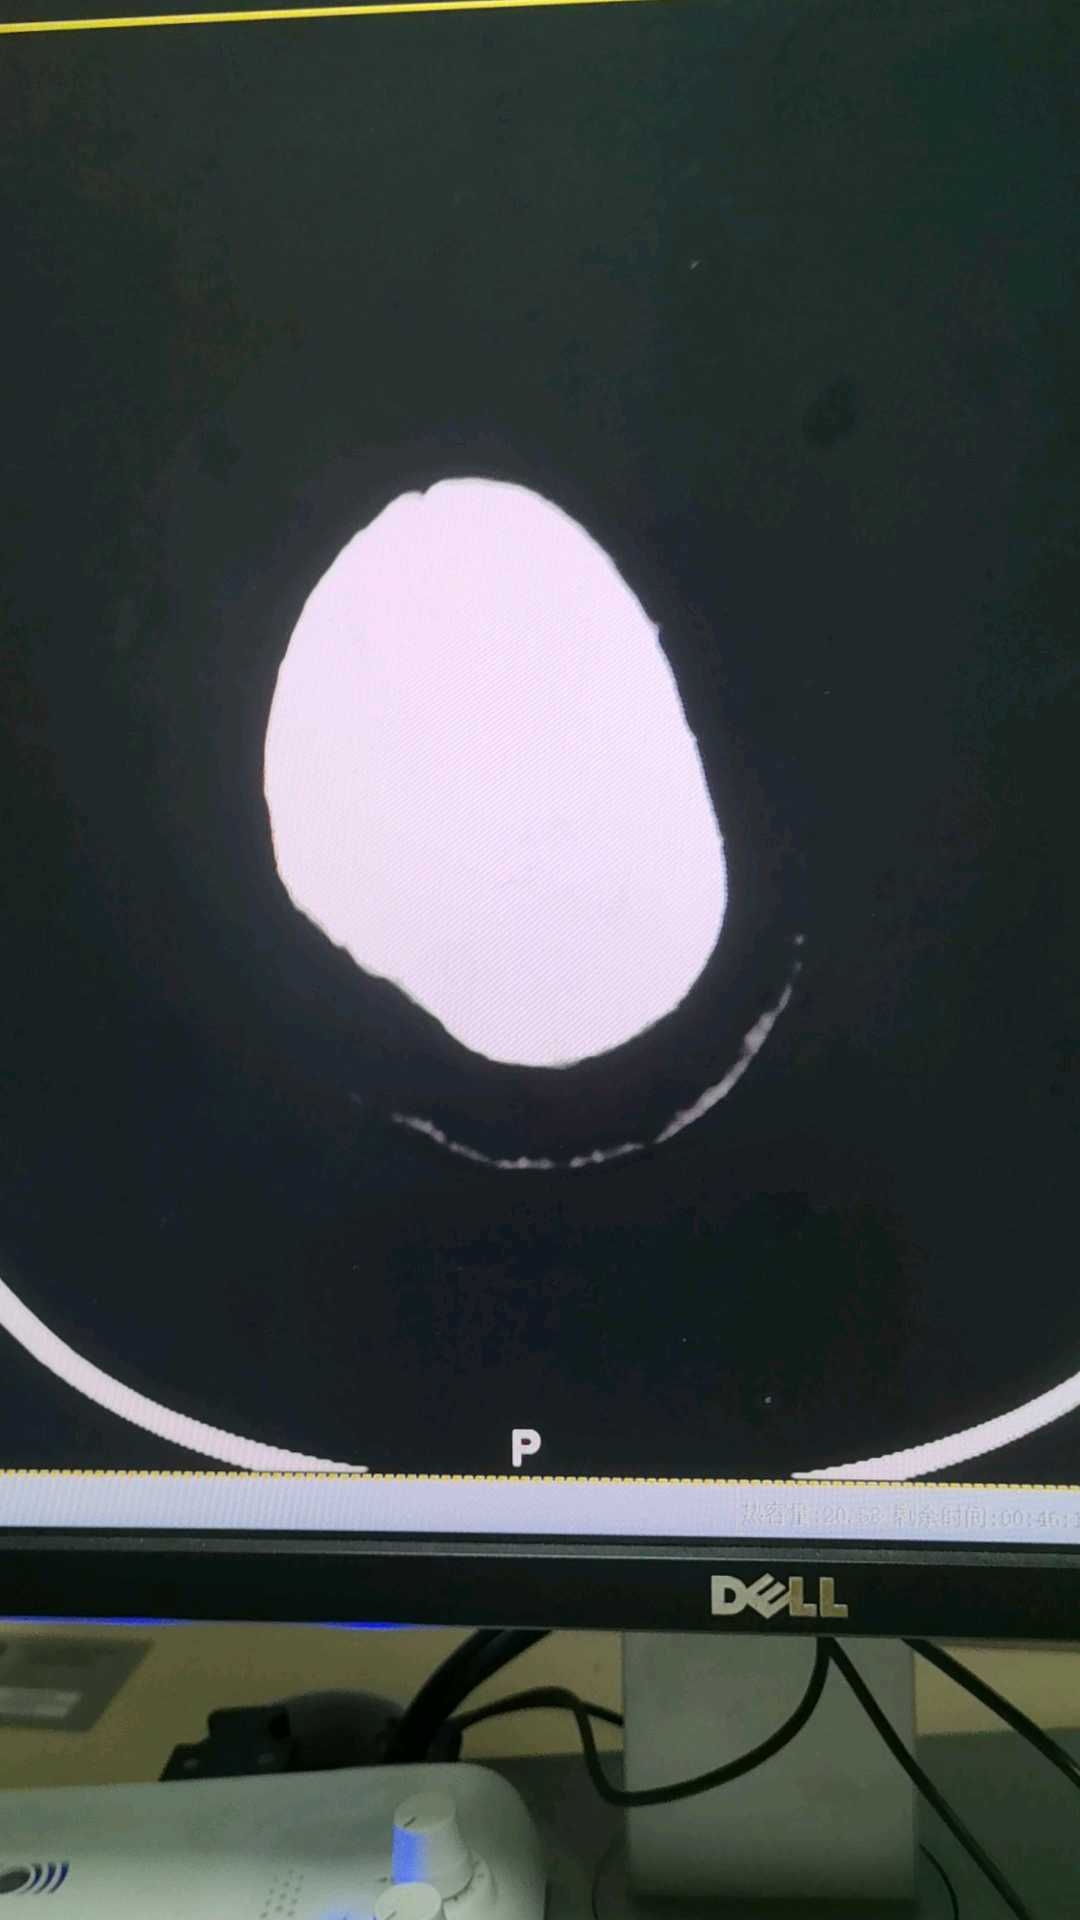

患者女 60y 哑巴  支支吾吾指着头部比划,医生开了头部CT

1.请问这是算扩张还是积水